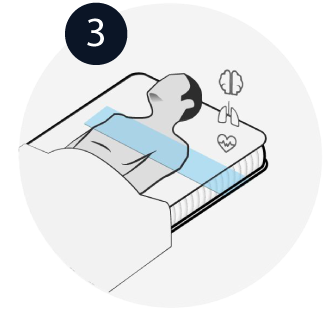

Sleep peacefully

Award winning contact free health monitoring technology that measures heart health, stress and sleep with clinical precision placed

under the mattress.

Placed under the mattress, Dozee monitors: